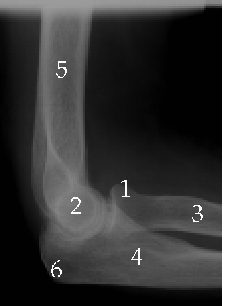

X-Rays

1. Head of Radius

2. Medial Epicondyle

3. Radius

4. Ulna

5. Humerus

6. Olecranon